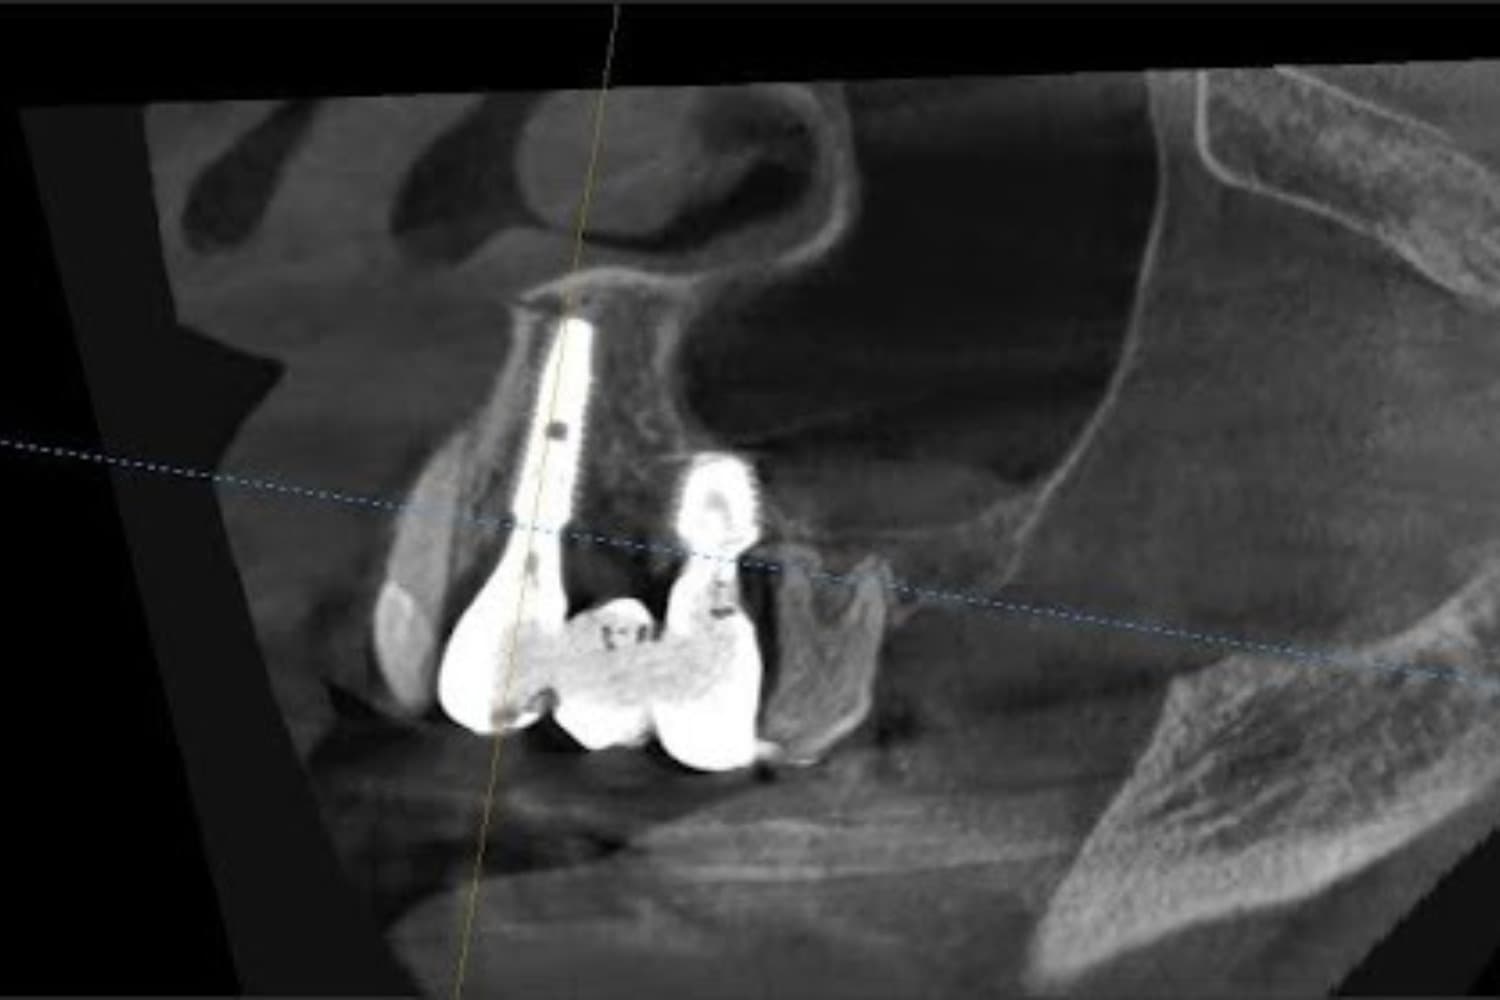

Short (短期間治療) 枚方市のインプラント治療 従来のインプラント治療では抜歯後3~6か月の期間を置くケースが少なくありませんが、当院では抜歯直後または抜歯後早期にインプラントを埋め込む手術を行っています。条件がそろえば、その日のうちに仮歯を入れることも可能です。 また当院ではEXOCADと呼ばれるCADソフトを導入しているため、上部構造(最終的な被せ物)を短期間で製作しやすい点も特徴です。 通常は噛めるようになるまで半年~1年程度かかるところ、当院なら抜歯後最短2か月程度、4~5回の通院で噛む力を回復できます。 Simple (シンプル) 枚方市のインプラント治療 インプラントを埋め込む部分の骨が少ない場合、これまではインプラント手術を行う前に、別途「GBR」「サイナスリフト」といった骨を作るための外科手術をしなくてはなりませんでした。 手術の機会が増えると、それだけ患者さまのお体や、時間・金銭面などのご負担が増えてしまうのは言うまでもありません。 当院なら抜歯直後や抜歯後早期にインプラント手術を行えます。このことにより、従来の大掛かりな骨造成術(GBR)を行わずに、インプラント手術をおこなうことが可能となりました。また、上顎の臼歯部に骨がない場合、従来のサイナスリフトでは、上顎洞に人工骨を入れ、その後、インプラントを埋入するという複雑な治療が必要でしたが、「エキストラショートワイドインプラント」と特殊な器具を使用することで、一回のインプラントの手術で終わらせることも可能となりました。 当院では追加の外科処置を不要にし、患者さまのご負担を減らしながら極めてシンプルなインプラント治療を行っています。 Small (最小限) 枚方市のインプラント治療 前述の通り、当院では追加の外科処置が必要ありません。さらに、従来よりも短めのインプラントを使用しています。そのため手術によるお体への影響が少なく、体に優しいインプラント治療を受けていただけます。 最小限の治療で、しっかりと噛めるお口を取り戻せるインプラント治療をご提供しているのが特徴です。 Safe(安全) 枚方市のインプラント治療 サージカルガイド インプラントを埋め込むあごの骨の中には、重要な神経や血管がたくさん通っています。それらを傷つけずに手術を完了させるには、事前の精密検査および診査診断が重要です。 当院では事前に必ず歯科用CTによる撮影を実施し、3次元的にあごの骨の状態を確認しています。これを元に、どのような角度でインプラントを埋め込むべきかシミュレーションを行います。 手術中の安全性をより一層高め、インプラントを正しく埋め込むために使うのが「サージカルガイド」と呼ばれる器具です。このガイドを作製することで、シミュレーション通りの角度・位置に埋め込めるよう注力しています。 また、専用のソフトを使ってインプラント治療後のお口の将来像も作成しています。患者さまにもご覧いただきますので、治療のイメージを掴みやすいのではないでしょうか。 衛生面でも、手術中に使用する器具はすべて個包装にし、高圧蒸気滅菌を実施。使用直前まで開封しませんので、清潔な器具で治療を行えます。こうしたさまざまな取り組みにより、安心・安全に治療を受けていただけるよう努めています。

親知らずの抜歯やインプラント治療で精密な診査診断ができるよう、通常のレントゲンに加えて歯科用CTを導入しています。 治療前には診査診断に加え、患者さまとしっかりお話をしてご不安やご要望を伺います。その上で、治療の理解を深めていただけるようアニメーションなどを用いて丁寧にご説明。治療前後には歯の写真を撮影し、患者さまご自身に仕上がりの確認をお願いしております。

左上の歯のインプラント治療(60代女性)

インプラント抜歯即時埋入・即時荷重(抜歯と同時にインプラントを埋入し、当日に仮歯を入れる)

重度の歯の動揺があり、何もしていなくとも痛みがある。治療にあたって前歯がないことを気にする。